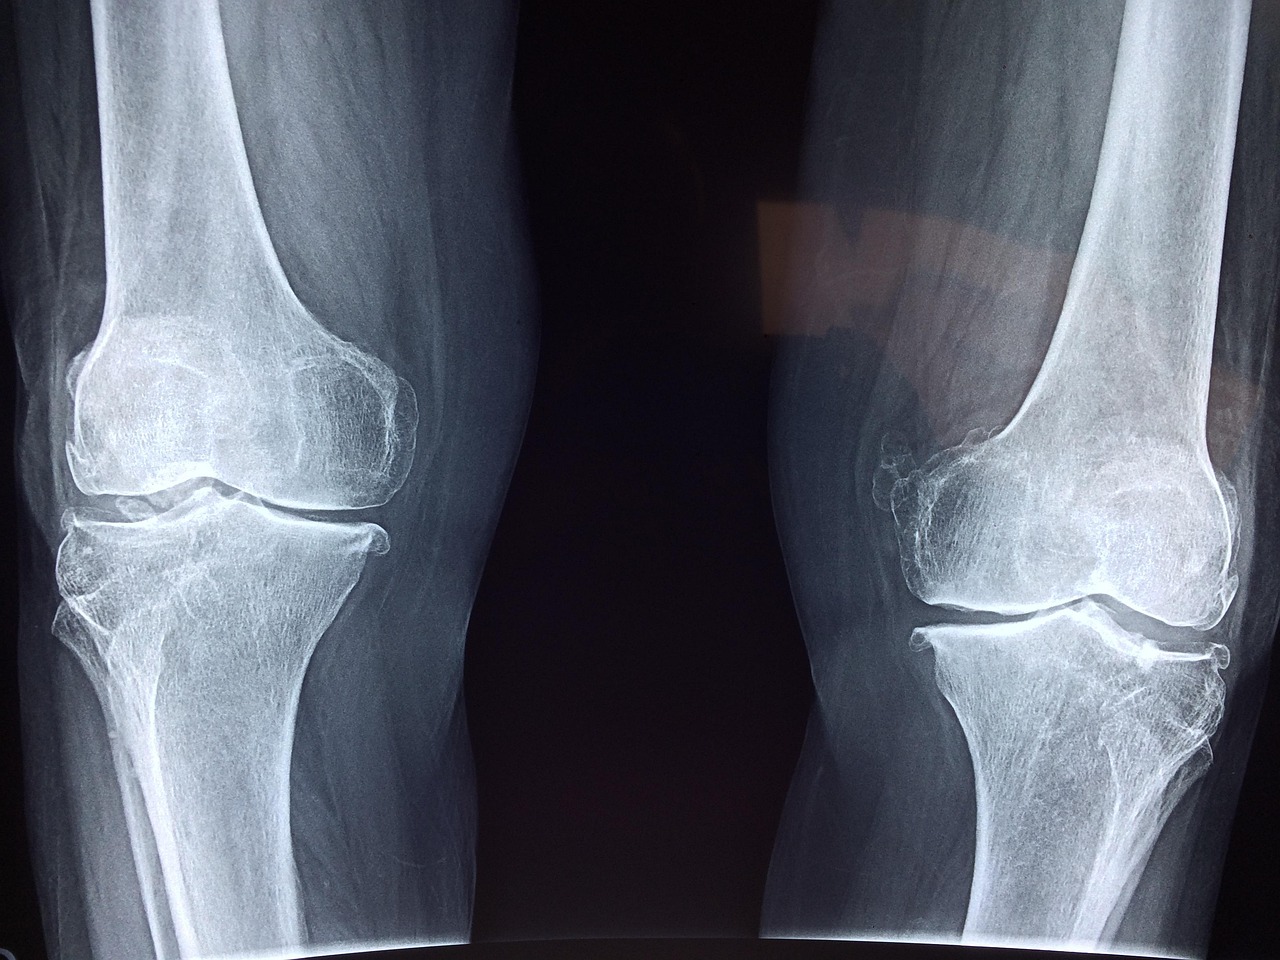

Sports medicine has witnessed significant advancements in recent times, particularly in the realm of cartilage repair surgeries. These innovations are crucial for athletes who suffer from cartilage injuries, as these injuries can severely restrict their performance and quality of life. Various surgical techniques have been devised to aid in the regeneration of damaged cartilage, helping athletes return to their sports quickly and effectively. Options such as microfracture, autologous chondrocyte implantation, and osteochondral autografts provide tailored solutions for different injury types. Moreover, researchers are exploring the use of biomaterials and scaffolding techniques to create an artificial environment for cartilage healing. The efficacy of these modern procedures is being assessed through various clinical trials, further contributing to the evolving landscape of sports medicine surgery. Each method varies in its approach and effectiveness, so understanding these options is essential for athletes seeking to make informed decisions regarding their treatment. Continuous research aims to improve these techniques, ensuring they offer the best possible outcomes for patients. This surge of innovation is positively impacting not only recovery times but also the long-term health of athletes’ joints.

Current techniques in cartilage repair emphasize minimally invasive surgical methods that reduce recovery periods while enhancing healing outcomes. One of the most notable advancements is the development of arthroscopic procedures, which allow surgeons to operate through small incisions. This technique minimizes tissue damage and leads to shorter rehabilitation periods for patients. Additionally, procedures like microfracture enable the creation of small holes in the bone to promote cartilage healing. This technique is popular due to its relative simplicity and effectiveness. Autologous chondrocyte implantation is another major breakthrough wherein a patient’s own cartilage cells are harvested, cultured, and then re-implanted back into the damaged area. This innovative method has shown promising results in regenerating cartilage with a more natural composition. Furthermore, advancements in synthetic biomaterials have also provided surgeons with tools to support chondral repair, offering further options for patients with severe cartilage deterioration. Technologies continue to evolve, and combined approaches, integrating cell therapy with scaffold technology, show promise in developing tissue-engineered solutions. As these techniques are refined, they contribute to enhanced functional outcomes for athletes following surgery.